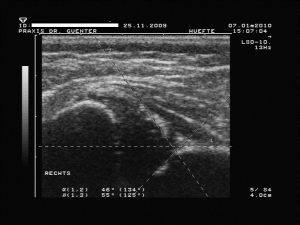

1. Linie (Grund- oder Basislinie bzw. -tangente: vom obersten Punkt der Fixierung des Perichondriums (so genannter Z-Punkt) am Ilium tangential nach distal bzw. ggf. eine Hilfslinie parallel am Rand der Schallauslöschung, welche auch schräg zu Bildkante sein kann!)

2. Linie (Pfannendachlinie bzw. -tangente: an Unterrand des Ileum und tangential an Unterkante des knöchernes Pfannendaches bzw. Erker)

und 3. Linie (Ausstell(ungs)linie: vom Umschlagspunkt der Pfannenkonkavität zur Konvexität durch die Mitte des Labrum).- Dadurch entstehen messbare Winkel (kranial zwischen Linie 1 und 2 der a-Winkel sowie kaudal zwischen 1 und 3 der b-Winkel) für die

Graduierung

- nach Graf mit dem Sonometer

Typ Ia bzw. b

ausgereifte Hüfte mit meist abgerundeten bzw. stumpfen und nicht unbedingt eckigem Erker (knöcherner Formgebung: gut, Erker: stumpf bzw. abgerundet oder eckig und Labrum: spitz oder schmal übergreifend, a-Winkel: > bzw. = 60°, b-Winkel: bei Variante a < bzw. = 55°, bei Variante b > 55°)